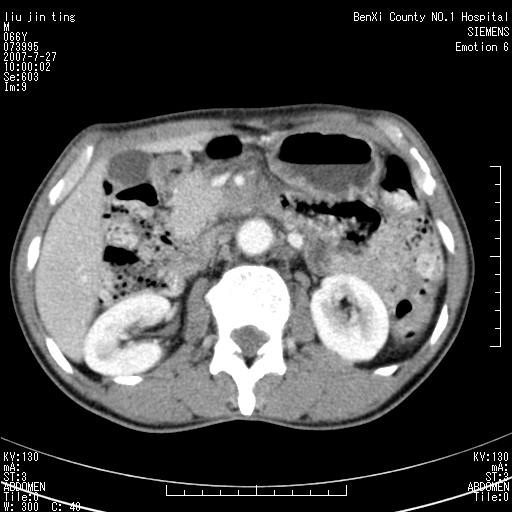

沿着肠系膜上动脉呈匍匐性生长的软组织肿块,形态不规则,包绕肠系膜上动脉,呈明显强化,考虑来源于肠系膜的恶性肿瘤

沿着肠系膜上动脉呈匍匐性生长的软组织肿块,形态不规则,包绕肠系膜上动脉,呈轻-中度强化,考虑来源于肠系膜的恶性肿瘤。

钩突是正常的,只见腹膜后淋巴结的肿大,考虑淋巴瘤或转移可能。

支持!恶性纤维组织细胞瘤可能,与淋巴瘤及淋巴结转移鉴别(腹主动脉周围清晰,其他部位亦未见明显肿大淋巴结)。